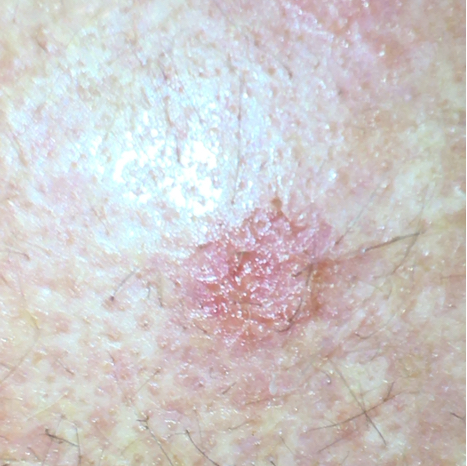

Exemplo de fotografia de queratose actínica

A queratose actínica torna frequentemente a pele de cor castanha-avermelhada com áreas elevadas e uma superfície áspera e crostosa. Isto deve-se ao facto de a tradução literal de queratose actínica significar cornificação da pele induzida pelo sol. A crosta é frequentemente de cor branca, mas também pode ser amarela ou castanha. As manchas têm frequentemente um tamanho de alguns milímetros a centímetros. Geralmente não apresentam sintomas, por vezes uma sensação de incómodo ou de comichão. Esta anomalia cutânea surge frequentemente no rosto, dorso das mãos, braços, pernas, decote, pavilhões auriculares ou, nos homens calvos, no couro cabeludo. Normalmente, existem várias áreas de QAs na pele.